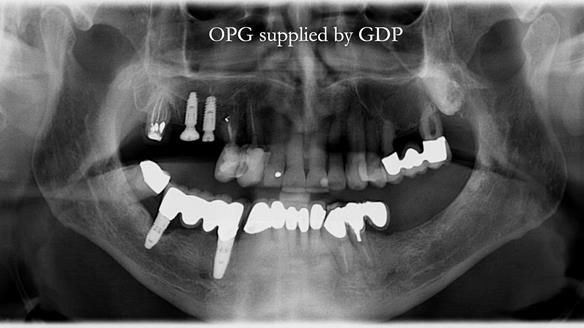

Like an increasing number of patients I now see (around 35% of referrals), Ken had implants that were failing or had already failed.

The starting point

We began with the lower jaw.

A posterior implant 47 had lost integration and was infected. This was removed.

The upper jaw

In the upper arch:

- a failing upper left tooth supporting a bridge was removed

- an implant-supported bridge on the upper right was dismantled